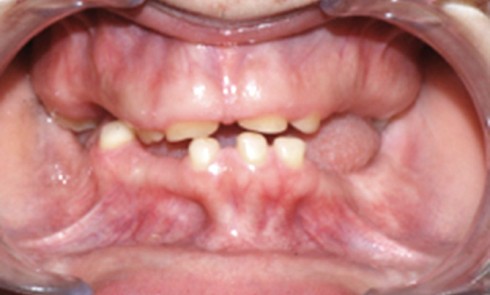

Les maladies rares, définies par une prévalence inférieure à 1/2000, sont au nombre de 9 000 et pour la grande majorité...